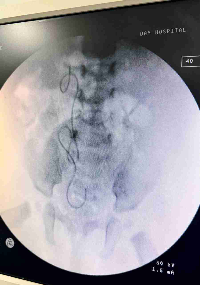

Olá Maya, nasceu com uma dilatação no canal urinário causando problemas no rim . Devido a isso causou uma dilatação de grau IV no rim direito, precisando de 2 cirurgia e de acompanhamento de pediatra. Uma cirurgia será feita agora com 3 meses de nascida para que seu canal urinário volte a funcionar normalmente será feita um corte para q ela faça xixi pela virilha para comprimir o canal urinário para voltar ao normal. Pois só poderá operar novamente com 2 anos de idade ,Onde será feita uma nova cirurgia para que coloque o canal novamente na bexiga para volte funcionar normalmente. O motivo que não pode fazer logo essa cirurgia direta pra bexiga é porque pode causar danos na bexiga por ela ser muito novinha e esta bem dilatado passando quantidade a mais de urina pro rim. Peço ajuda e colaboração com qualquer valor apenas para uso de remédios exames  procedimentos cirúrgico. Exames de cintilografia  e cistoscopia  UCGM  custa qase 9 mil reais fora a cirurgia.  Como não temos condições financeiras nesse momento peço ajuda com qualquer valor ou divulgação.  018.472.352-39  pix Daniela macedo    69993740086 wats